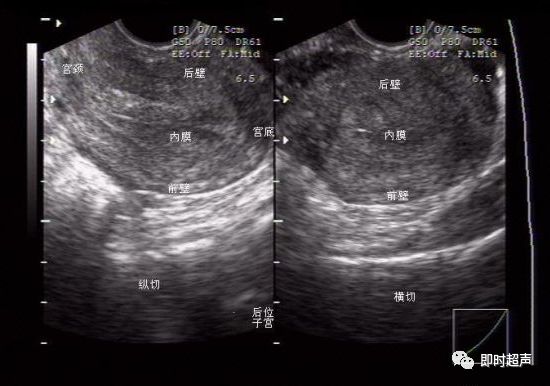

1.阴超最大的难度是方向问题,要非常清楚探头的位置和方向,以探头上标向上纵切子宫:左为腹侧,右为背侧,近场为宫颈,远场为宫底。

子宫前后位的判断主要看宫底是靠近腹侧(前位)还是背侧(后位),如果纵切时图象怎么打也是个横切的图象,那子宫就是水平位,因为子宫与声束平行,这时要左或右侧偏一点,使声束方向改变。探头横切时,主要看探头在盆腔的位置,因为阴超视野较小。探头偏向左显示的就是左侧盆腔,反之亦然。如果习惯了阴超的方向,其实和经腹部看一个道理,慢慢体会就行。

A显示阴超纵切,子宫呈前倾/前屈,并在监视器上显示。图像由声束进入人体后旋转90度而得。声束顶端(狭窄部分)在探头表面,经90度旋转后出现在图像的上方。腹部超声和阴超都可显示前腹壁(a)。B 横切前倾/前屈的子宫,图像见上。由探头逆时针旋转90度而得。同样由声束进入人体后旋转90度而得。子宫右侧(r)出现在图像左侧。